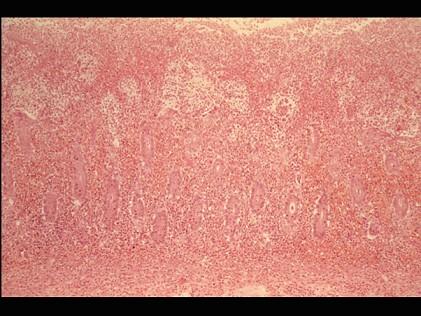

问题 根据图,关于菌痢的病理改变正确的是 ( )

选项 A.黏膜充血、水肿、中性粒细胞和巨噬细胞浸润 B.粘膜下层、肌层、浆膜层有明显的炎症反应 C.假膜主要为纤维素、坏死的肠粘膜、细菌、嗜中性粒细胞及红细胞等,部分有脱落 D.整个肠粘膜有假膜覆盖,粘膜上皮及腺体大片消失 E.大约一周左右,假膜开始脱落,形成大小不等,形状不一的“地图状”溃疡如图

答案 ABCDE